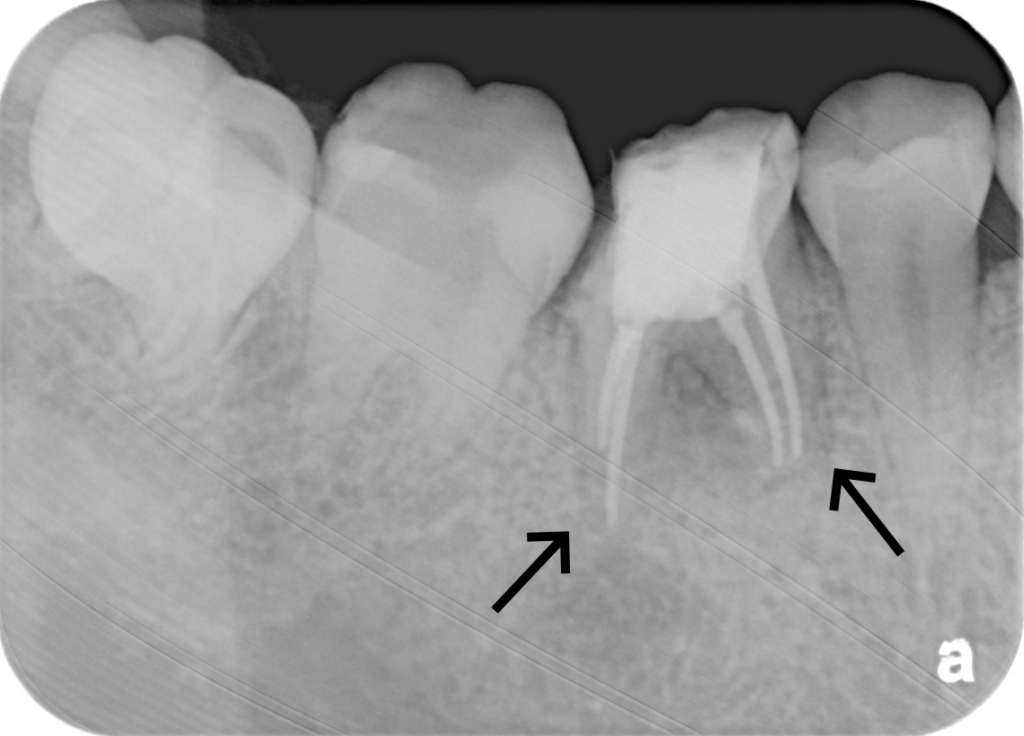

右下がかむと痛い・むし歯治療希望とのことで来院されました。 右下6番は根管内に感染を起こして根尖部に透過像を認めました。 根尖病変が非常に大きく、根管も複雑な形態をしていたため、まず歯科用CTを用いて3次元的な診断をしたのち、ルーペを使用して感染源の徹底的な除去および精密な根管治療を実施しました。 術後の経過は良好で、透過像も消失しています。根管治療後は、強度と審美性を兼ね備えたジルコニアクラウンで最終補綴を行いました。

| 概要 | 前歯に穴が開いているので治療して欲しい・右下がかむと痛いとのことで来院されました。 右下6番は根管内に感染を起こして根尖部に透過像を認めました。 根尖病変が非常に大きく、根管も複雑な形態をしていたため、まず歯科用CTを用いて3次元的な診断をしたのち、拡大ルーペを使用して感染源の徹底的な除去および精密な根管治療を実施しました。 術後の経過は良好で、透過像も消失しています。根管治療後は、強度と審美性を兼ね備えたジルコニアクラウンで最終補綴を行いました。 |